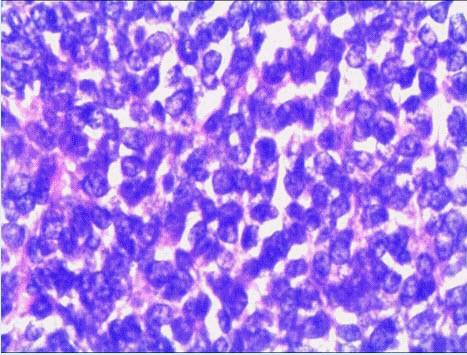

提示光镜下肿瘤细胞形态如图所示.

光镜下可见,对照组hct15细胞形态无变化